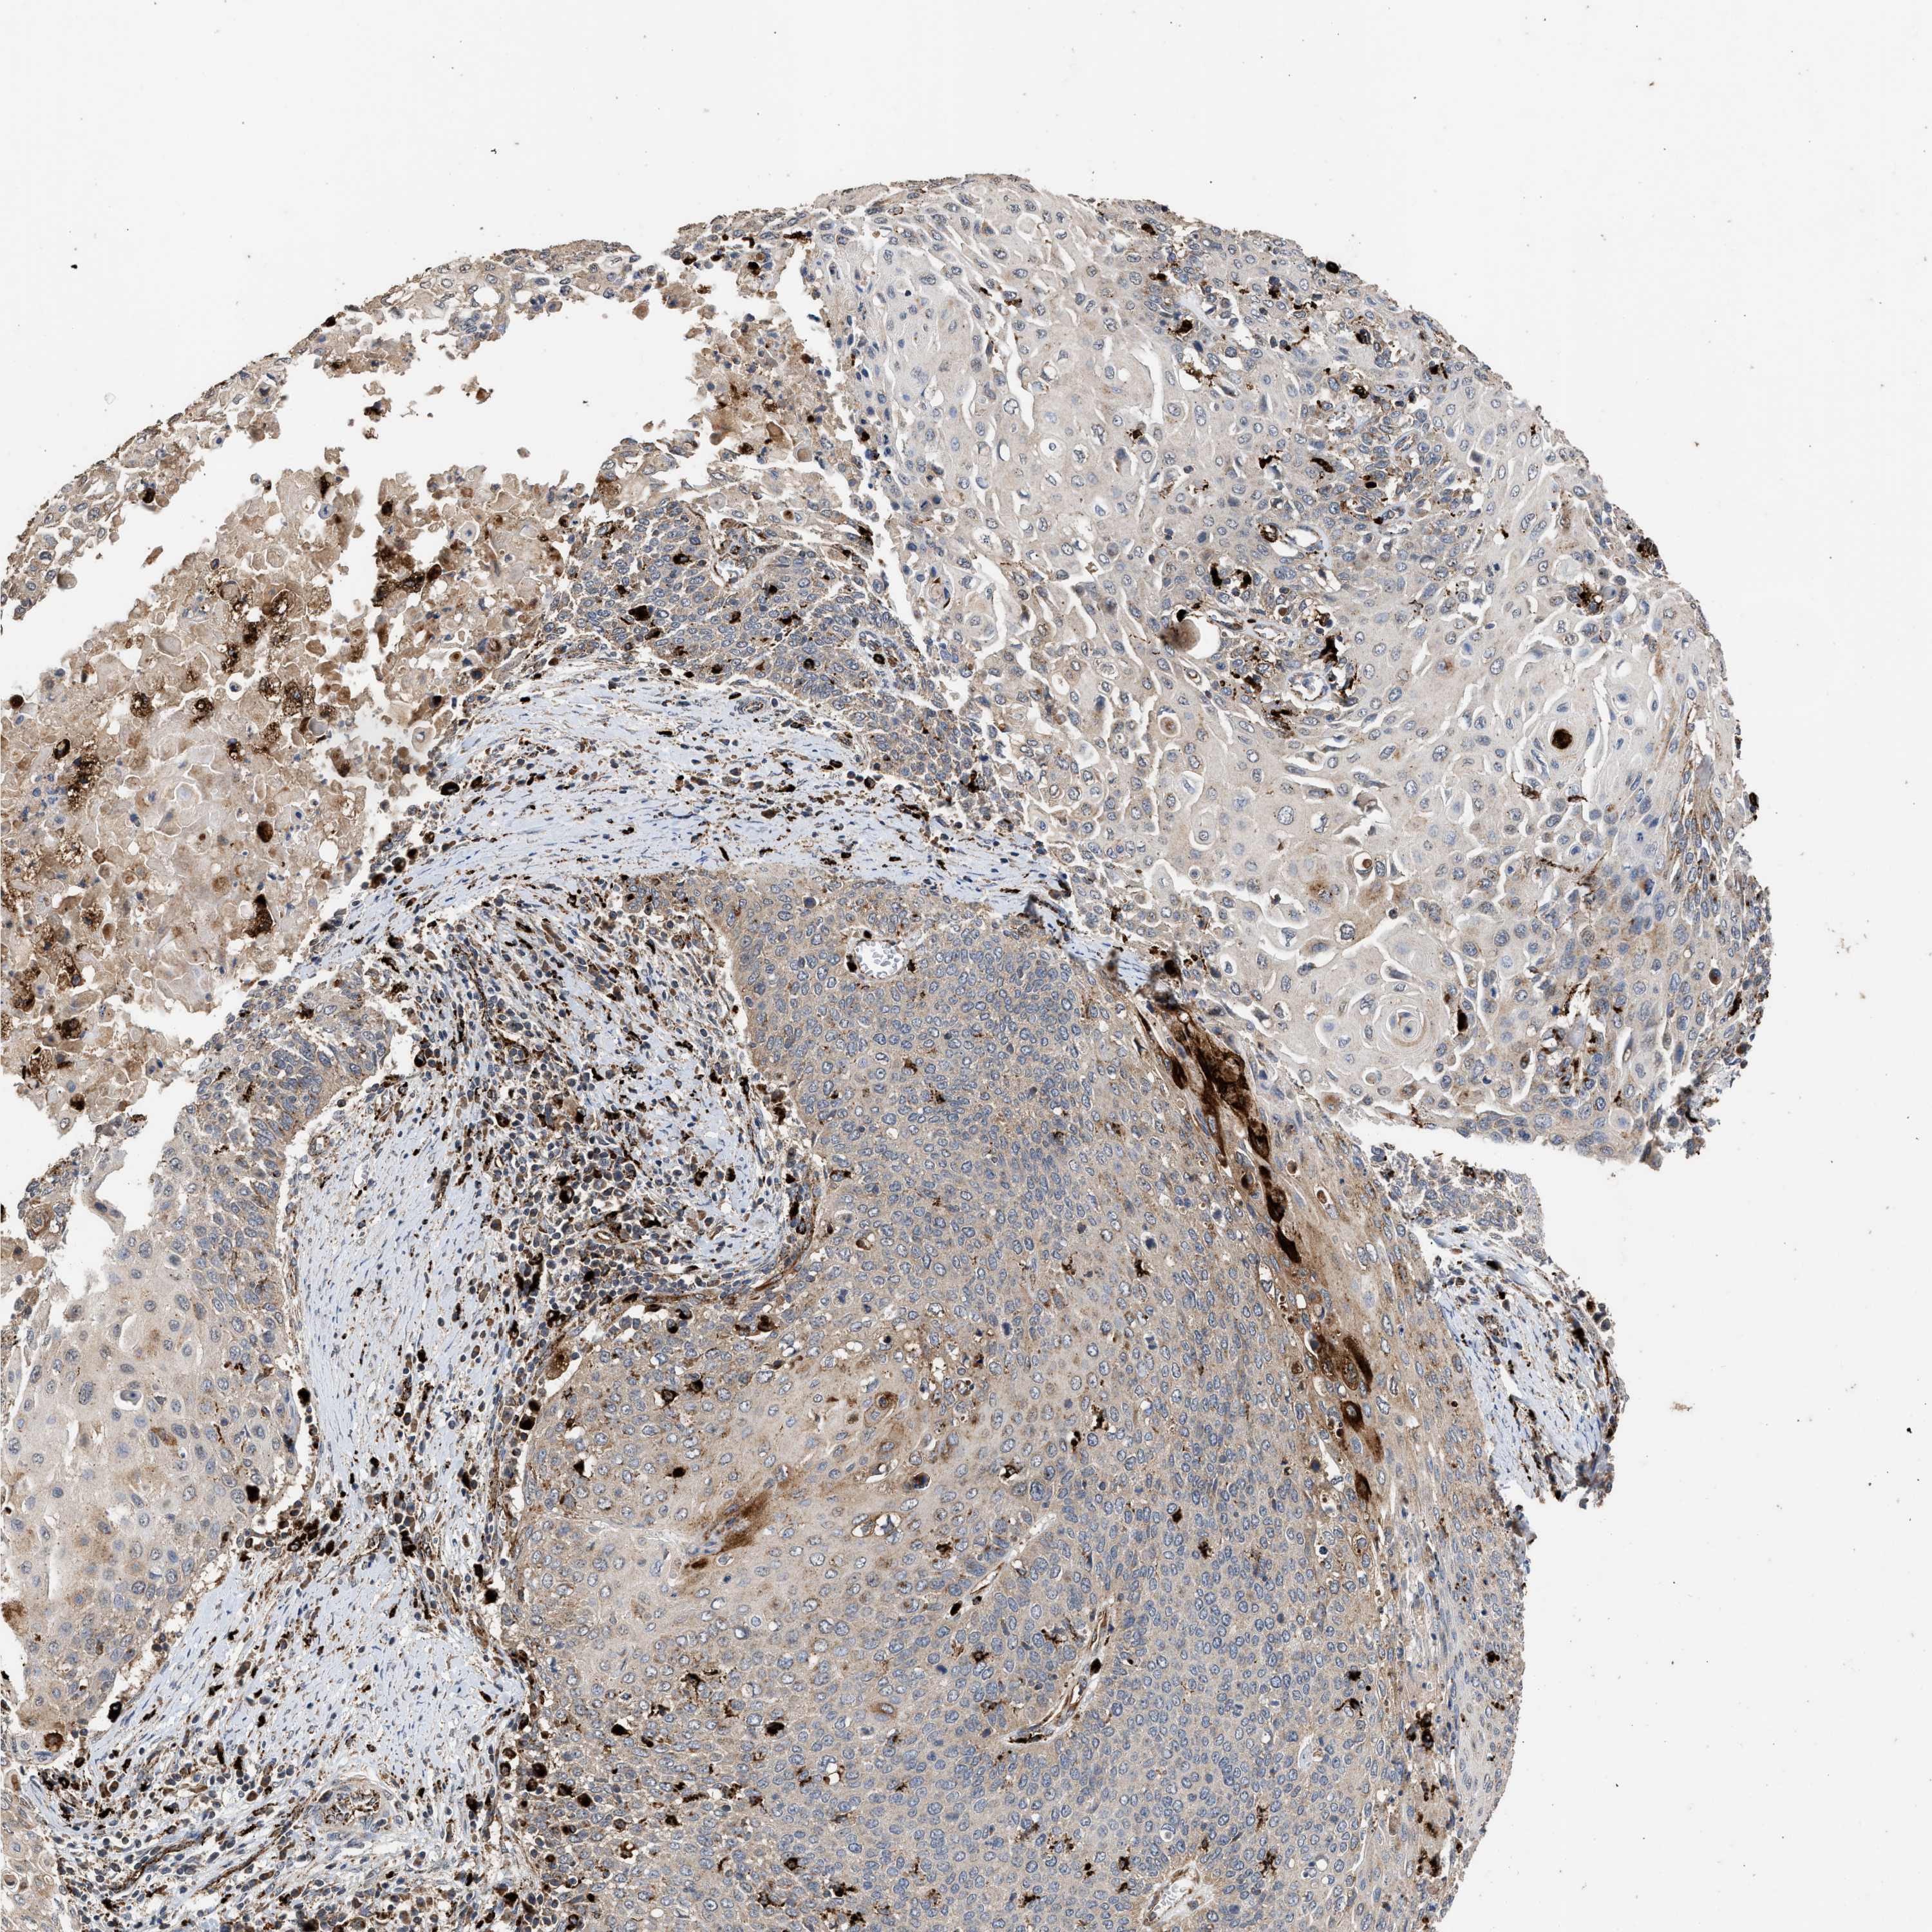

CERVICAL CANCER - Protein expressioni

A mouse-over function shows sample information and annotation data. Click on an image to view it in a full screen mode. Samples can be filtered based on level of antibody staining by selecting one or several of the following categories: high, medium, low and not detected. The assay and annotation is described here.

Note that samples used for immunohistochemistry by the Human Protein Atlas do not correspond to samples in the TCGA dataset.

Antibody stainingi

Antibody staining in the annotated cell types in the current human tissue is reported as not detected, low, medium, or high, based on conventional immunohistochemistry profiling in selected tissues. This score is based on the combination of the staining intensity and fraction of stained cells.

Each image is clickable and will lead to virtual microscopy that enables deeper exploration of all samples and also displays staining intensity scores, fraction scores and subcellular localization as well as patient and tissue information for each sample.

Antibody CAB017112

Staining

High

Medium

Low

Not detected

Intensity

Strong

Moderate

Weak

Negative

Quantity

>75%

75%-25%

<25%

None

Location

Nuclear

Cytoplasmic/membranous

Cytoplasmic/membranous,nuclear

Squamous cell carcinoma, NOS

Adenocarcinoma, NOS